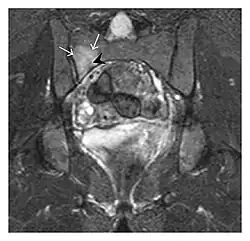

The sacrum is usually masked by overlapping bowel gas in conventional radiographs, and the subtle radiographic findings are usually nondiagnostic and even misleading. The characteristic "H" pattern has been correlated with biomechanical models of patient activities. The vertical parasagittal planes correspond to the region of maximal stress during walking, while the horizontal fracture develops later, secondary to the loss of lateral support by parasagittal fractures. MRI is the primary imaging technique in this case, with the most common MRI pattern showing bone marrow edema and a fracture line (Figure 12). Coronal views are quite contributive in sacral fractures, allowing the detection of the horizontal component, especially with fluid-sensitive sequences. Although the sacrum is the most commonly involved, pelvic insufficiency fractures are often multiple, and other typical locations should be mentioned.[1]

Proximal femoral fractures usually occur in osteoporotic patients, and their signs include subtle neck angulation, trabecular angulation, and subcapital impaction line. A frog-leg lateral view may be helpful if the greater trochanter is short enough. However, positioning can be difficult because of hip pain. In patients with strong suspicion of proximal femoral fracture and negative radiographs, MRI limited to coronal T1 W images and scintigraphy can be highly valuable (Figures 13 and 14). Such an option, with limited examination time, is cost-effective and allows reliable exclusion or confirmation of the diagnosis, preventing an unnecessary stay at the hospital or delayed treatment. Moreover, MRI helps to detect soft tissue abnormalities which are more frequently seen in femoral, acetabular, and pubic injuries than sacral lesions. Concomitant fractures are also frequently seen in typical pelvic sites.[1]

-

a -

b

Figure 13: Partial osseous avulsion of the gluteal muscles at the greater trochanter in a 59-year-old man who presented with the right hip pain without a history of trauma. Lauenstein view and anteroposterior and radiographs (not shown) did not show an obvious fracture line or disruption of bony contours in the acetabulum or the right femoral neck. (a) Coronal T1-weighted MRI displays an incomplete fracture line extending partially from the greater trochanter (arrow). (b) Coronal short tau inversion recovery MRI shows heterogeneous hyperintensity in the same region (arrow) as well as hyperintensity within the gluteus medius and minimus muscles (arrowheads) consistent with tissue edema and hematoma.[1]

Figure 14: Subcapital insufficiency fracture in a 55-year-old man with a left hip pain without a history of trauma. Anteroposterior and Lauenstein view radiographs centered on the left hip do not show an obvious fracture line, but mild acetabular osteophytosis was noted consistent with hip osteoarthritis (not shown). (a) Coronal T1-weighted MRI shows a linear low-signal band through the femoral neck corresponding to a fracture line (arrowheads). (b) Bone scintigraphy shows focal uptake (arrow) corresponding to the fracture.[1]